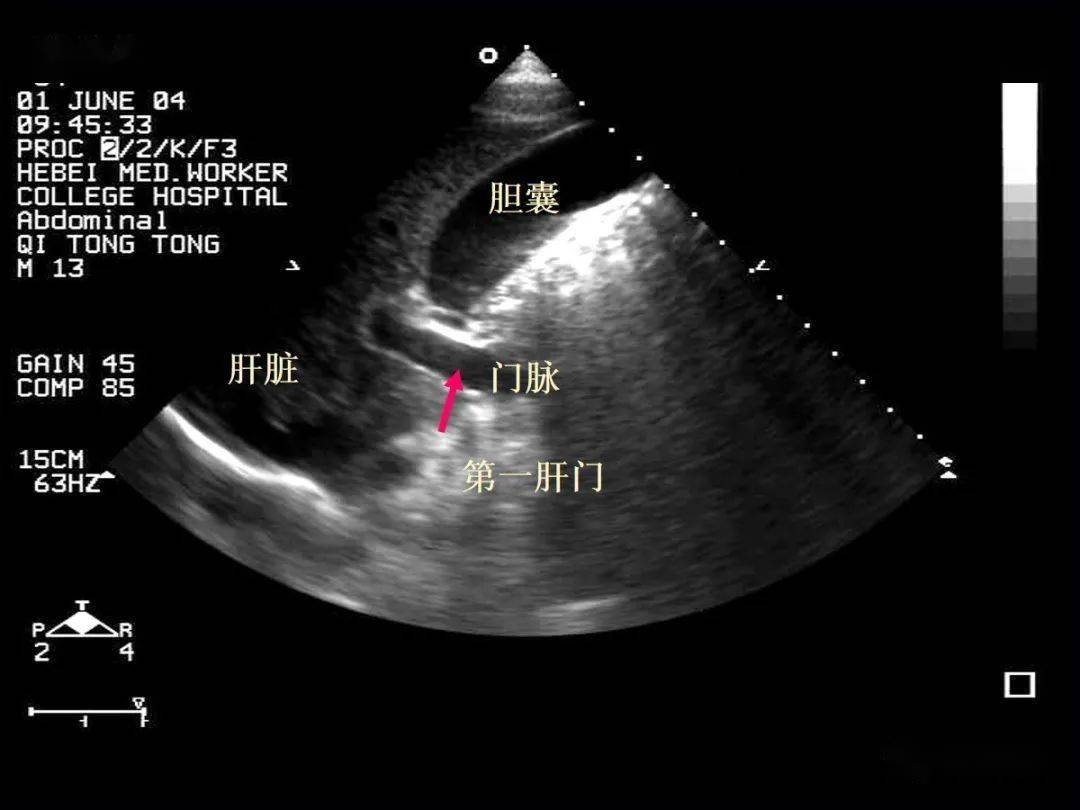

小肠系膜(sma和smv)(一)胃内探查sma发至腹主动脉,位于腹腔干(celiac